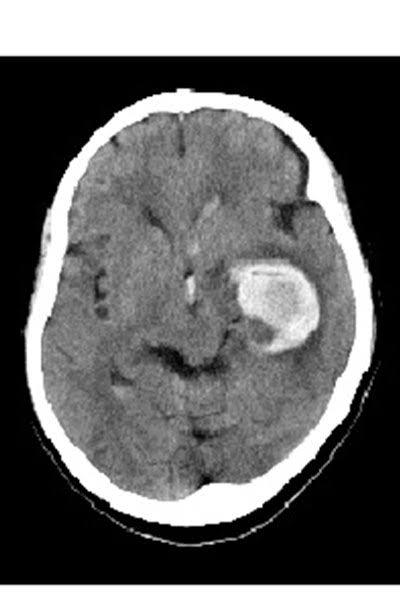

アンパンマン断面図

鬼太郎のレントゲン写真